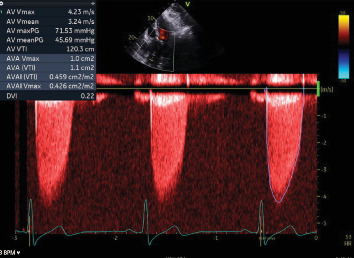

摘要冠状动脉异常起源是一种罕见的先天性心脏缺陷。随着心脏计算机断层扫描和磁共振成像技术的应用,冠状动脉异常的检测可能会增加。一旦发现异常冠状动脉,手术干预的建议取决于患者的症状、应激成像上是否存在诱导性缺血以及高危解剖特征。77岁男性,有高血压、高脂血症、慢性肾脏病III期和中度主动脉狭窄病史,表现为非st段抬高型心肌梗死,横断面成像发现右冠状动脉主动脉起源异常。他的主动脉狭窄也从中度发展到重度,目前尚不清楚他的心肌梗死是否完全归因于主动脉深度狭窄背景下的供需差异,或者他异常的冠状动脉解剖结构是否可能是导致他出现这种情况的罪魁祸首。一个多学科的心脏小组决定进行经导管主动脉瓣置换术,如果他的心绞痛症状在瓣膜置换术后持续存在,然后重新对他的右冠状动脉异常进行手术干预。

Anomalous aortic origin of a coronary artery is a rare congenital heart defect. The detection of anomalous coronary arteries is likely to increase with increased availability and application of cardiac computed tomography and magnetic resonance imaging. Once detected, the recommendation for surgical intervention on anomalous coronary arteries depends upon patient symptoms, the presence or absence of inducible ischemia on stress imaging, and high-risk anatomic features. A 77-year-old man with a history of hypertension, hyperlipidemia, chronic kidney disease Stage III, and moderate aortic stenosis presented with a non-ST-elevation myocardial infarction and was found to have an anomalous aortic origin of the right coronary artery on cross-sectional imaging. His aortic stenosis had also progressed from moderate to severe, and it was not clear whether his myocardial infarction could be exclusively attributed to a supply-demand disparity within the context of profound aortic stenosis or if his aberrant coronary anatomy could be implicated as the culprit for his presentation. A multidisciplinary heart team decided to proceed with a transcatheter aortic valve replacement and then readdress surgical intervention on his anomalous right coronary artery if his anginal symptoms persisted following valve replacement.